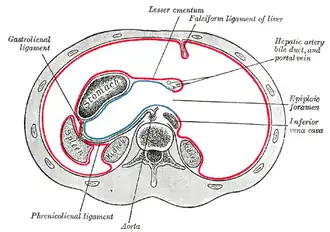

Horizontal disposition of the peritoneum in the upper part of the abdomen

Horizontal disposition of the peritoneum in the upper part of the abdomen -